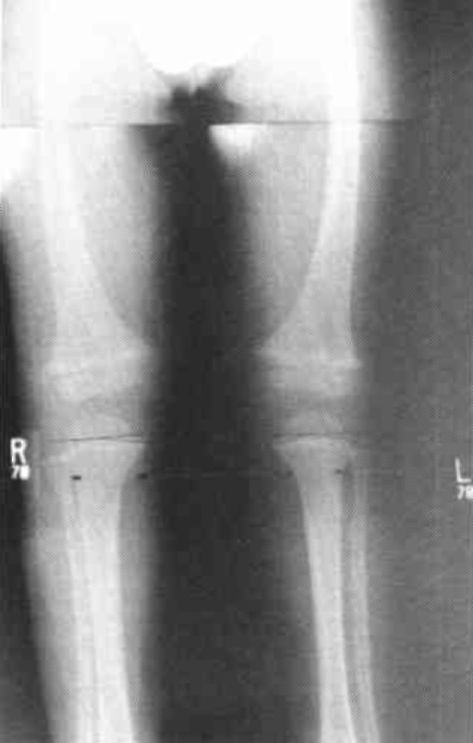

A white male, age 3, was presented at the orthotic clinic by his parents because of bowing of his right lower extremity (Fig. 4). Clinical examination showed bilateral tibia vara. Bilateral standing AP radiograms were obtained. The E-M angle determined on these radiograms was 20° bilaterally (Fig. 5). The child was fitted with the bilateral KAFO's (Fig. 6A) and a new set of standing AP radiograms was obtained which showed no difference in the E-M angle at that time (Fig. 6B).

Figure 4. Clincal appearance of B.D. at age 3 with bilateral Blounts Disease.Figure 5. Standing A/P radiograms show E-M angles of 20° bilaterally.